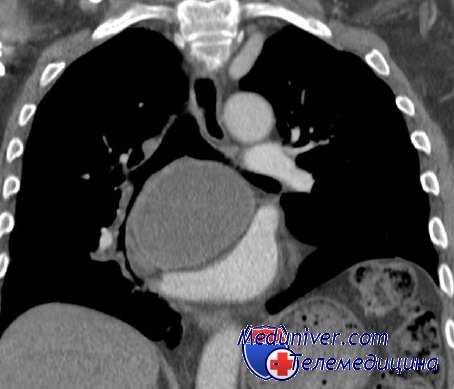

Показания к проведению повторной операции представлены в табл. 2. Рецидив порока сердца в большинстве случаев (43 пациента, 47,8%) был вызван прогрессированием ревматического процесса с фиброзной деформацией и кальцинозом створок клапана, подклапанных структур и фиброзного кольца. У 10 больных за прошедшие годы после операции сформировался порок ревматической этиологии на неоперированном клапане. Среди причин дисфункции механических протезов клапанов были выявлены: тромбоз (см. рисунок на цв. вклейке) - 16 (17,8%) случаев, паннус - 14 (15,6%), парапротезные фистулы - 13 (14,4%). Рисунок 1. Обструкция механического клапана сердца тромбом. У 10 больных образование парапротезных фистул было связано с протезным инфекционным эндокардитом, у 3 признаков эндокардита выявлено не было.